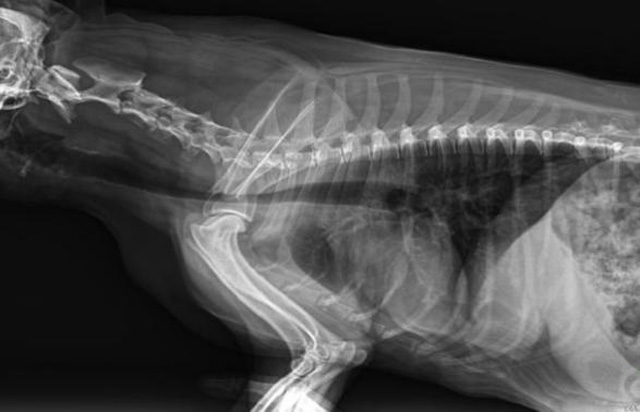

从临床角度出发,大力发展动态DR,以精准的诊断为小动物保驾护航。宠物DR升级使用双焦点球管,大尺寸平板探测器,超高频逆变高压发生器。医用纤维板台面,防止宠物划伤。宠物DR整机小巧实用,骨略结构和器官位置,分类详细,运算更快,让拍摄条件更科学,有助于提高诊断的准确性和效率。安装移动非常方便。低输入电流设计,220伏常规电压。多品种动物程序设定,满足各个临床需求。成像效果显著,宠物不能言语表达,导致误诊率居高不下。宠物诊疗均以经验诊断为主的方式,确保最小化辐射降低对医生及动物的影响。以满足精细化的宠物医疗需求,成为诊断宠物内外科疾病的必备工具。使医院更有竞争力,为医院创收增光添彩。